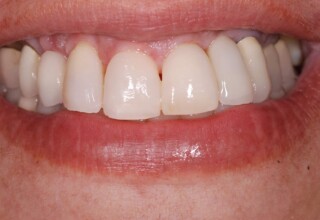

Porcelain Veneers

The best way to solve esthetic problems of the anterior teeth. They combine very little tooth grinding with very high esthetic performance. In the following extensive case anterior teeth presented with: old restorations, staining, poor shape, length and tooth –gingiva ratio. Meticulous diagnostic waxing was performed on study casts and temporary veneers were manufactured. Temporary veneers were used intraorally to evaluate the incorporated changes and to further modify and adjust were needed. When esthetics and function were approved by the patient and were satisfying for the operator the temporaries were used as a guide for the final porcelain veneers. The five final veneers on the upper anterior teeth restored the smile of the patient to almost perfection.

Initial appearance

Final appearance